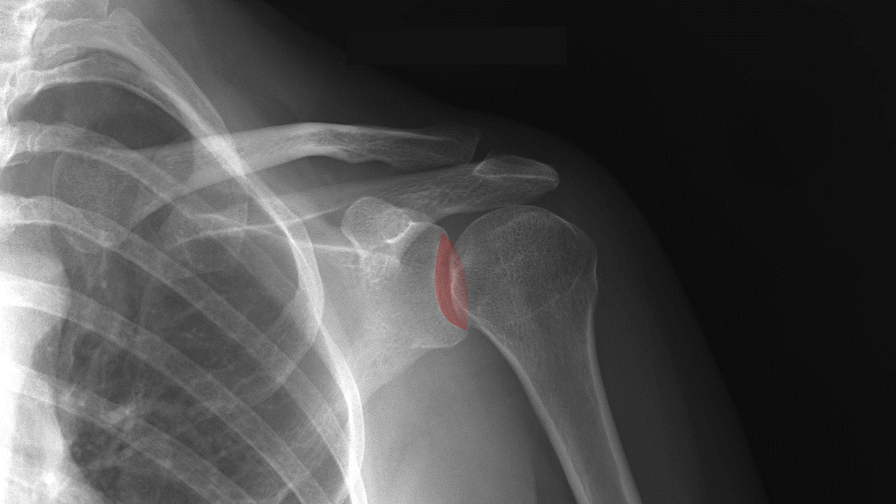

В Нидерландах хирург-ортопед доктор Корнелис Виссер из лейдердорпской больницы поставил своему пациенту напечатанный на 3D-принтере протез плеча и суставной впадины лопатки. Если все будет хорошо, то пациент должен обрести полную подвижность в области плеча.

Технология 3D-печати позволила врачам создать абсолютно уникальный протез, который «сел» практически идеально.

«За несколько недель до операции мы сделали КТ-скан плеча пациента, – рассказывает доктор Корнелис Виссер. – На его основании было получено 3D-изображение. С его помощью мы смогли определить наилучший вариант размещения протеза и заказали в США индивидуальный молд. Прежде с расположением протеза приходилось определяться буквально по ходу операции. Теперь я пользуюсь индивидуальным молдом. Я могу подстроиться под анатомию каждого пациента».

После окончания операции новое плечо пациента ведет себя гораздо естественнее традиционных протезов. Оно лучше двигается, и нагрузка на сустав распределяется равномерно. Благодаря этому, оно прослужит намного дольше обычных протезов, хотя этому и нет фактического подтверждения, ведь установка 3D-печатных протезов – это относительно новая практика.

Это первый случай, когда в Нидерландах установили 3D-печатный протез плеча. Ранее технологию трехмерной печати использовали при изготовлении протезов колена.